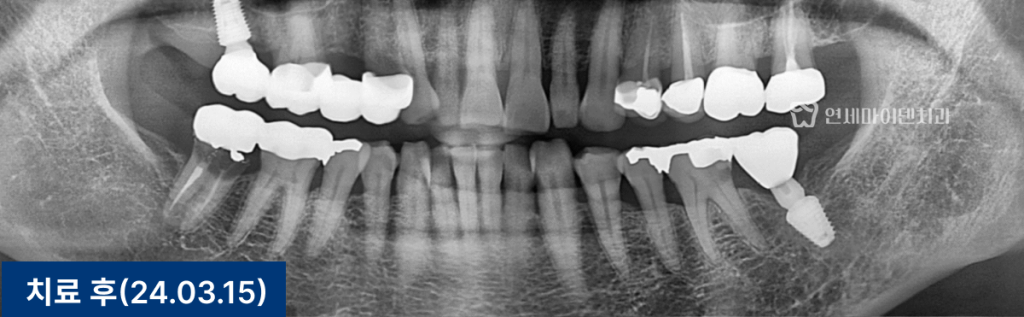

환자분의 왼쪽 아래 어금니(#36)는

기존 금 인레이 아래로 2차 충치가 발생한 상태였습니다.

통증이 동반되었으며, 충치 깊이가 신경에 도달해

신경치료가 불가피한 상황이었습니다.

신경치료를 통해 염증 부위를 제거하고,

레진으로 내부를 밀봉한 뒤 크라운을 수복했습니다.

치근까지 염증이 진행되기 전 내원하신 덕분에

발치 없이 치아를 보존할 수 있었습니다.

반대편 어금니(#46)는

스플린트 크라운으로 수복되어 있었습니다.

겉으로 보기엔 멀쩡했지만,

내부에는 깊은 충치가 진행돼 있었습니다.

보철물을 제거하자 치아 내부 조직이 심하게 손상되어 있었고,

결국 보존 불가로 판단했습니다.

이에 따라 발치 후 즉시 임플란트를 진행했습니다.

다행히 치조골 상태가 양호해 즉시 식립이 가능했습니다.